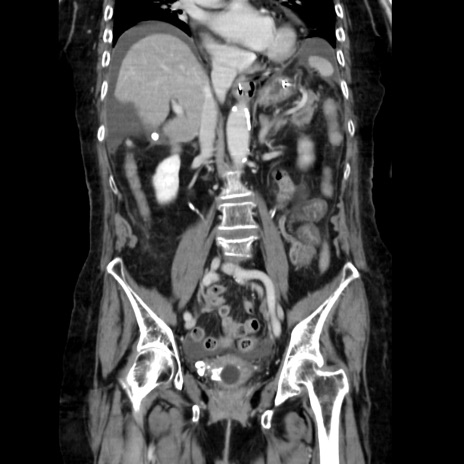

症例40(冠状断像)

【症例】90歳代女性

【主訴】腹痛・嘔吐

【現病歴】 食欲低下、嘔吐があり昨日他院受診。肺炎と診断され入院となる。入院後より腹部全体に圧痛あり。胃管留置され経過みていたが、症状持続するため、

当院転院となる。

【既往歴】胸椎圧迫骨折、胆石症

【身体所見】腹部:中央に激痛あり、圧痛あり、反跳痛不明

【データ】WBC 17100、CRP 18.82

横断像